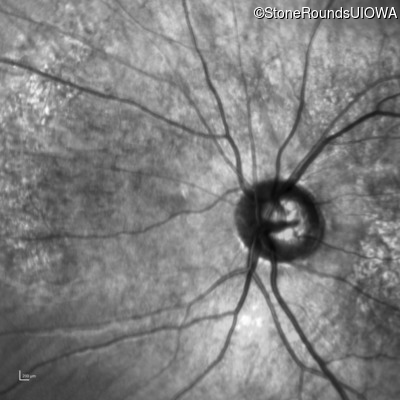

Infrared Fundus Photograph - Right - 10/200

Exemplar